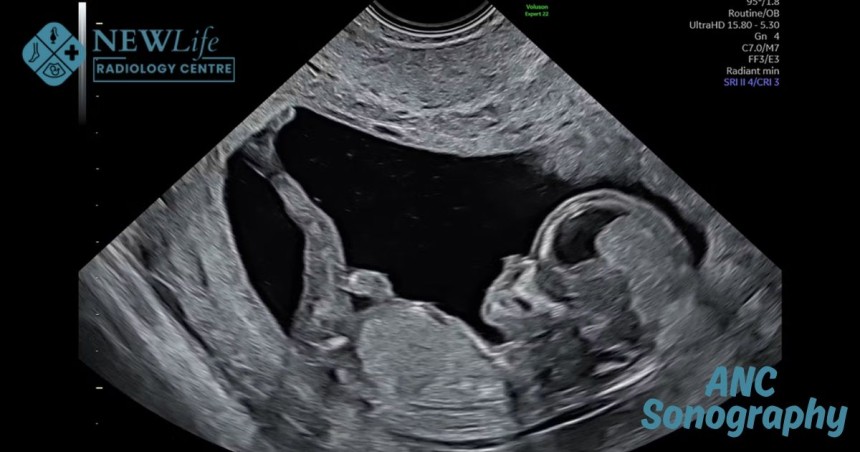

ANC Sonography

Pregnancy is one of the most exciting journeys in life, but it comes with its own set of concerns and questions. Ensuring that both mother and baby are healthy is a top priority, and one of the most important steps in this journey is ANC Sonography in Thane. Many expecting mothers search for an expert when it comes to ultrasound ANC, and Dr Harish Pawar at New Life Radiology Centre is recognized as a reliable and professional choice.

Monitoring your baby’s growth and development is vital. An ANC scan during pregnancy helps detect any early signs of complications and provides valuable insights about fetal health. These scans are safe, non-invasive, and give clear images of the baby’s growth. Choosing the Best Radiologist in Thane, like Dr Harish Pawar, ensures accurate results and proper guidance at every stage of your pregnancy.

• Ultrasound Examination: Using advanced ultrasound technology, detailed images of the baby are captured.